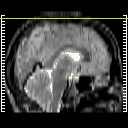

glioma overlay -- Slice #27

[Home][Help][Clinical] Slice 27